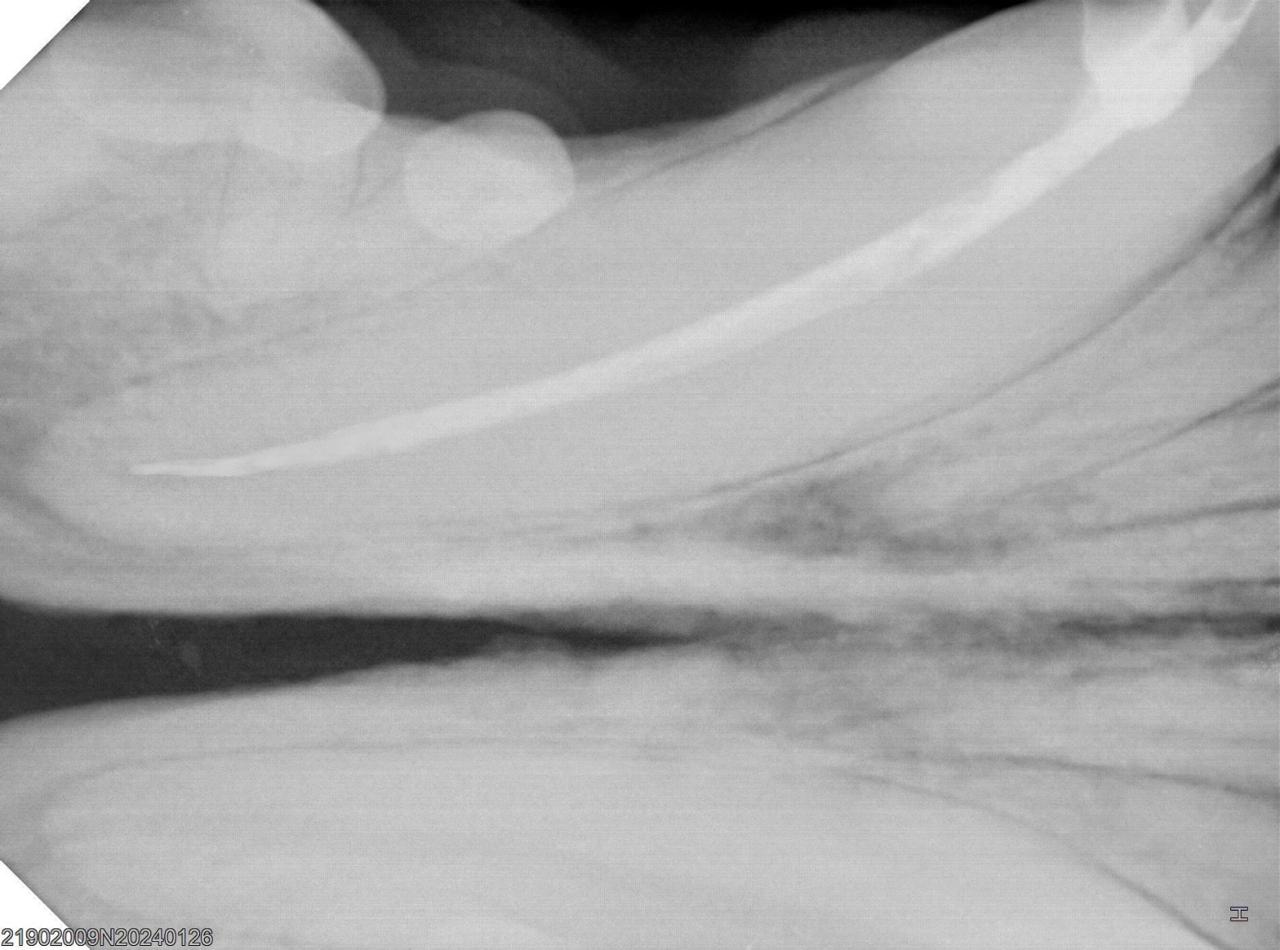

La endodoncia es un tratamiento dental que consiste en extraer la pulpa (nervio) de un diente dañado o infectado, limpiar el interior de los conductos radiculares y sellarlos para salvar la pieza dentalConocido coloquialmente como «matar el nervio», este procedimiento evita la extracción del diente y se realiza cuando caries profundas, fracturas o golpes han causado una infección irreversible en la pulpa

Proceso de la endodoncia

• Extracción de la pulpa: El odontólogo accede al interior del diente para retirar la pulpa, que incluye los nervios y vasos sanguíneos.

• Limpieza y desinfección: Se limpian y desinfectan los conductos radiculares para eliminar cualquier bacteria o infección.

• Sellado: Los conductos se rellenan y sellan con un material biocompatible, como la gutapercha, para prevenir futuras infecciones.

• Restauración

Finalmente, se reconstruye la corona del diente para devolverle su forma y funcionalidad.